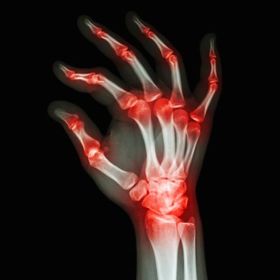

Artritis Reumatoide

La artritis reumatoide es una enfermedad crónica, sistémica y autoinmunitaria, clínicamente se caracteriza por ser una poliartritis crónica simétrica, destructiva y erosiva. Afecta prácticamente a cualquier articulación, pero de manera predominante a pequeñas articulaciones de las manos.

Manifestaciones Clínicas

Artralgias matutinas. Articulaciones metacarpofalángicas e interfalángicas afectadas. Inflamación de las sinoviales. Protuberancias firmes denominadas nódulos reumatoides. Xeroftalmia, xerostomía y xerodermia (Sintomas secos)